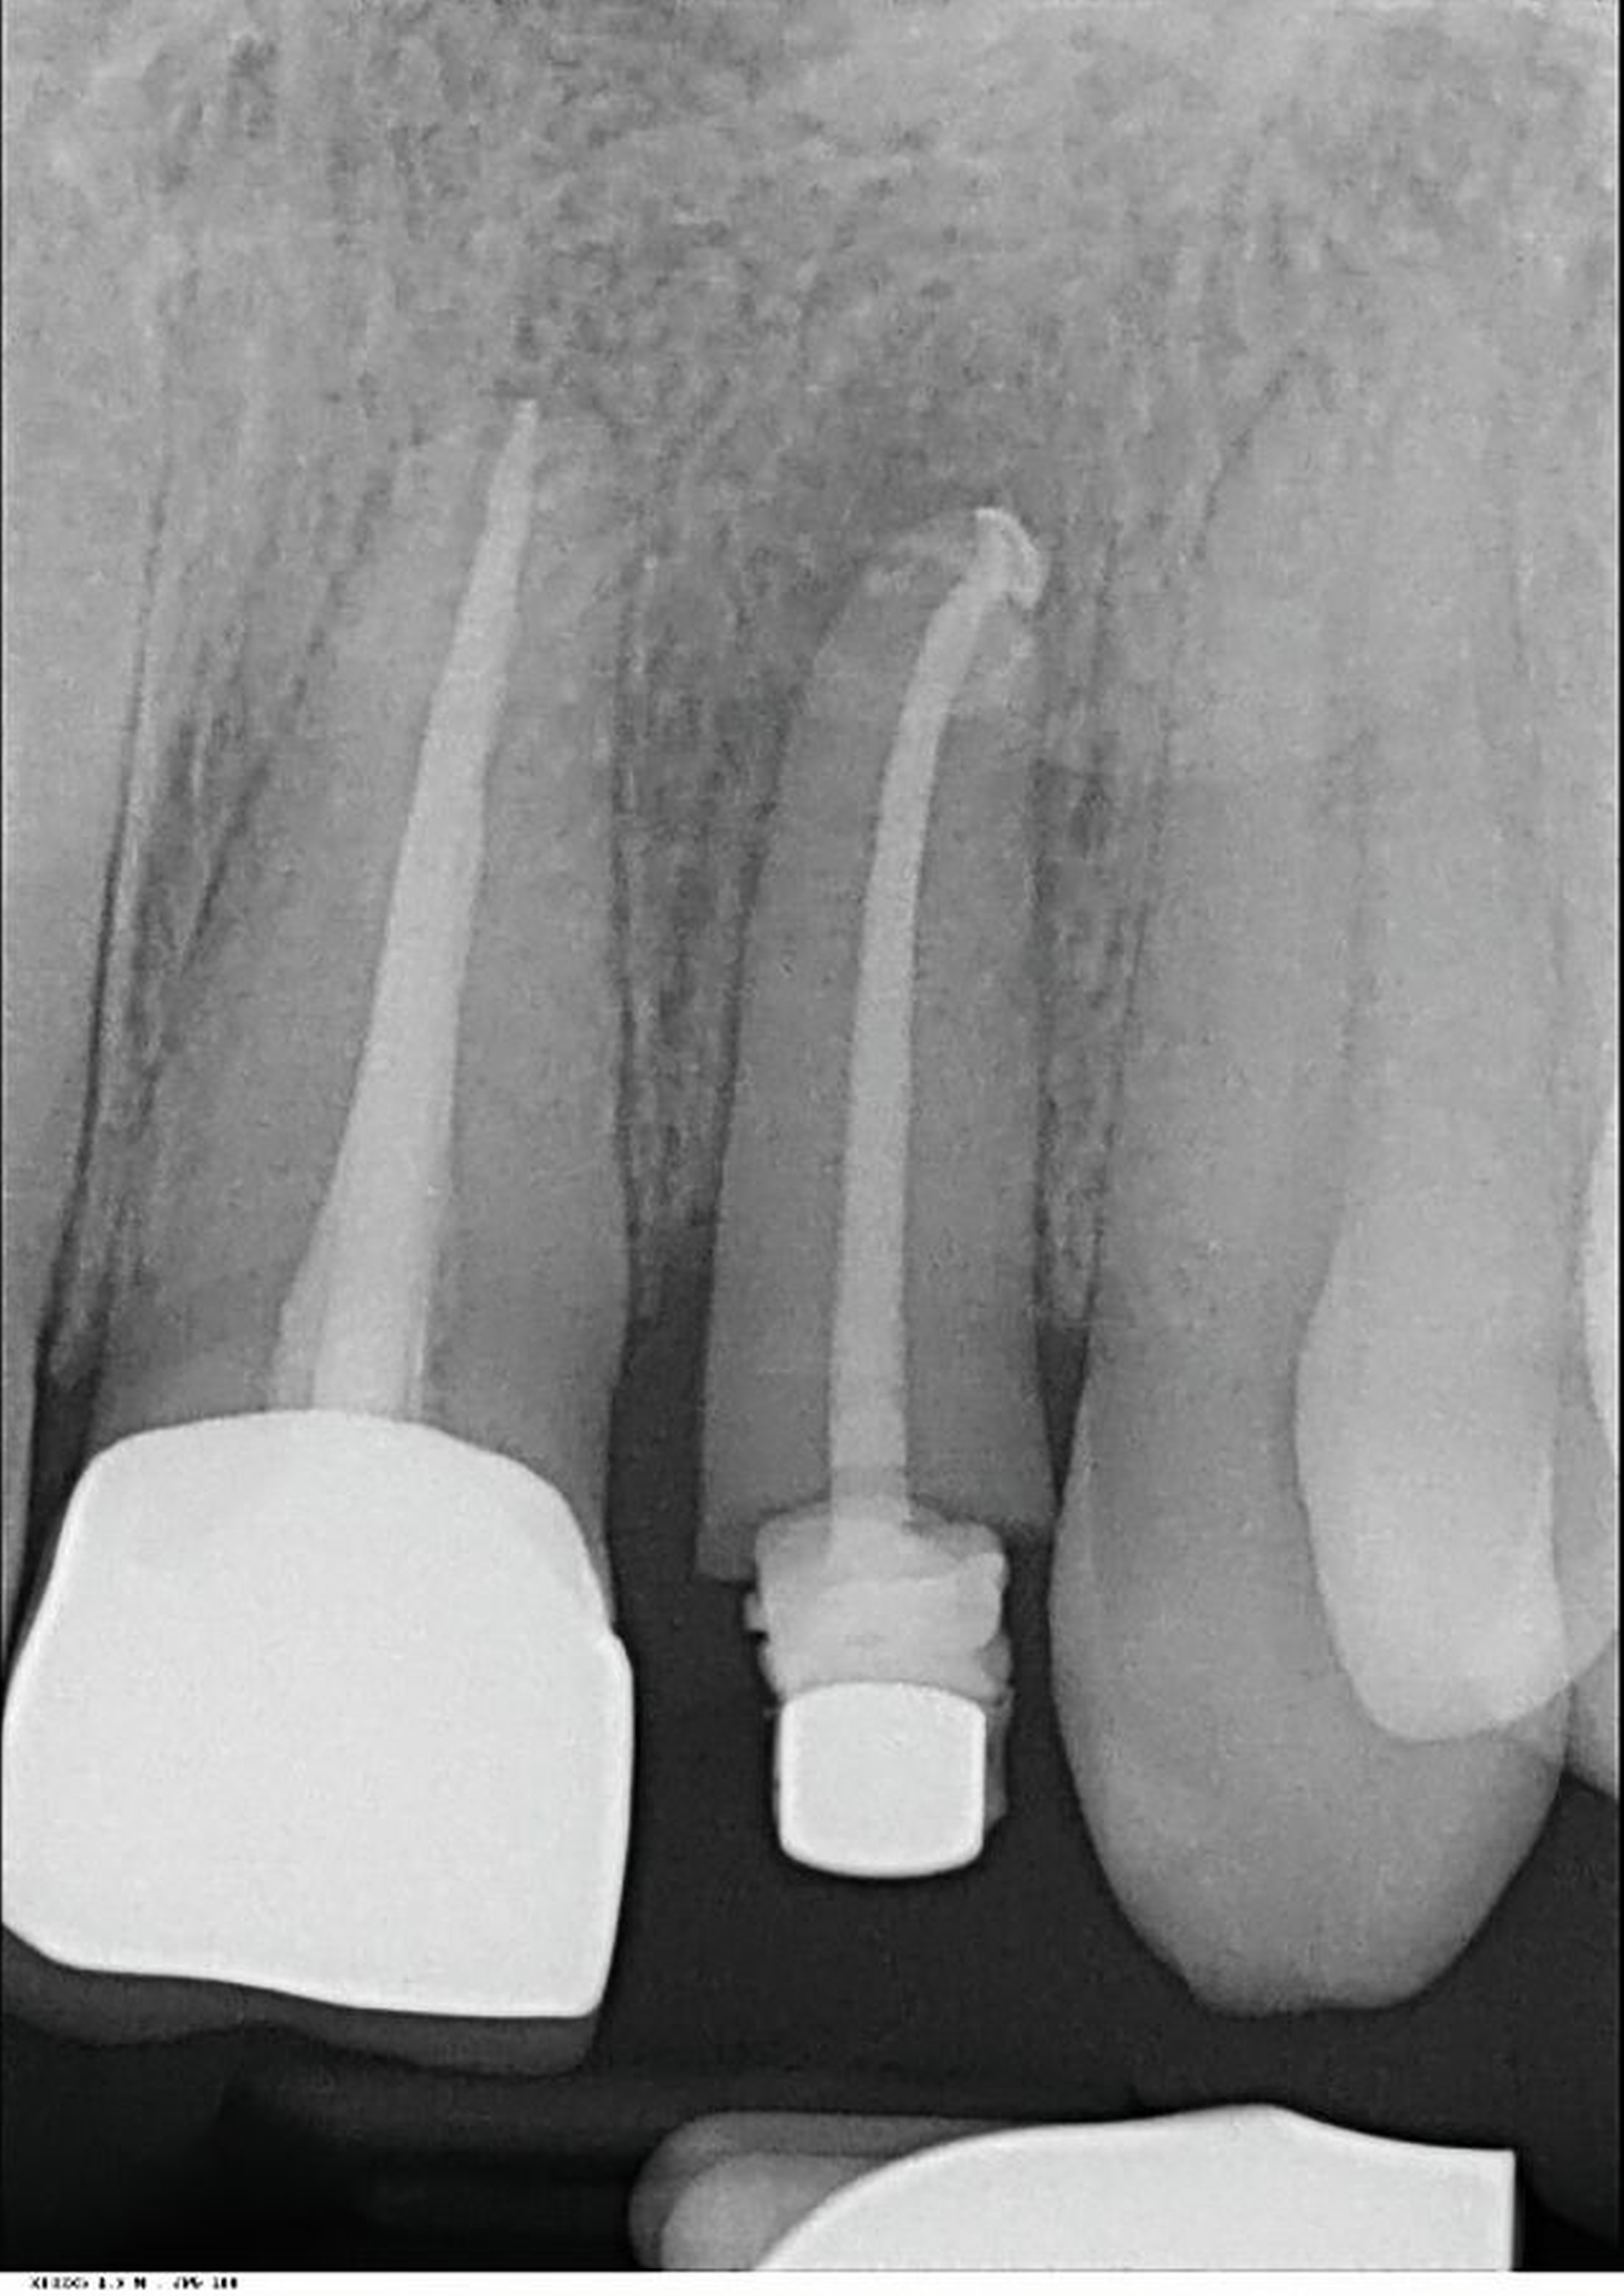

Dem Patienten war der Erhalt der natürlichen Dentition wichtig. Dementsprechend wurde er darüber aufgeklärt, dass Zahn 11 aufgrund des tiefen Frakturverlaufs nicht ohne weiteres restaurativ versorgt werden kann. Deshalb wurde zusammen mit der Poliklinik für Kieferorthopädie die Extrusion des Zahnes – ohne kieferorthopädische Behandlung der Malokklusion – geplant. Da Zahn 11 Symptome einer irreversiblen Pulpitis zeigte, bestand die Indikation zur endodontischen Therapie (Abbildung 9).

In der zwischenzeitlich angefertigten Einzelzahnaufnahme sind die orthopädisch bedingten Umbauprozesse anhand eines deutlich erweiterten Parodontalspalts und an der Verlagerung des Zahnes nach koronal zu erkennen (Abbildung 13). Auffällig ist, dass approximal ein Knochenumbau stattgefunden hat, was im Rahmen der kieferorthopädischen Extrusionstherapie zu erwarten war.